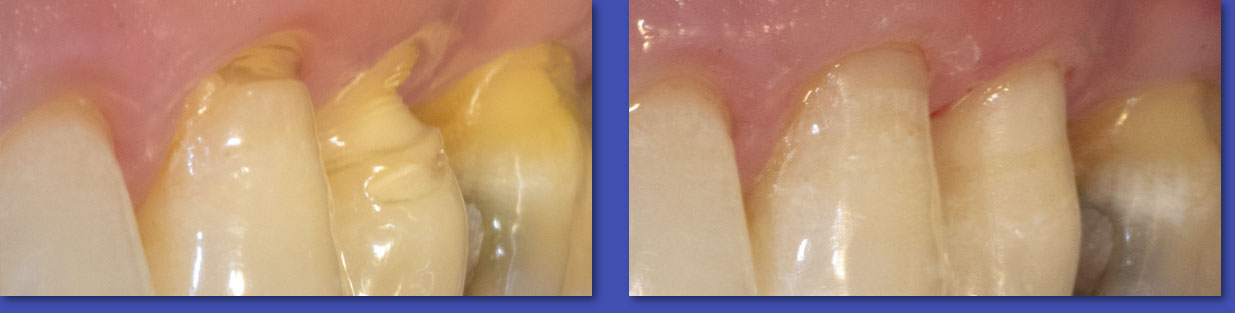

1.  OPERATORIA DENTAL

La Operatoria Dental se dedica a la restauración de los dientes dañados en forma parcial producto de caries, traumatismos  y otras lesiones no cariosas (atrición, abrasión, erosión, hipoplasias de esmalte, etc.). Hoy en día estas restauraciones se realizan en material de resina llamados “composite” que imitan el color del diente y han dejado casi obsoletas a las restauraciones metálicas y amalgamas.

ANTES

DESPUÉS